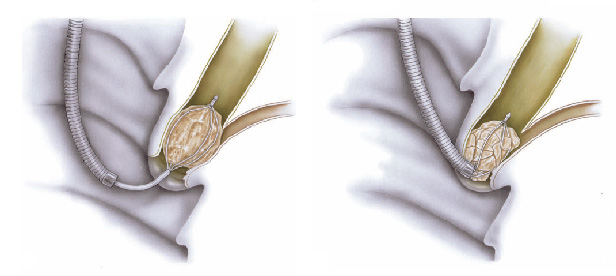

A ligadura elástica é considerado o melhor procedimento para o tratamento das varizes de esôfago. Estas surgem em pacientes que possuem pressão aumentada da veia porta (hipertensão portal) que possui várias causas sendo a principal delas a cirrose hepática.

O procedimento é realizado para a prevenção da ruptura deste vasos evitando assim quadros de hemorragia digestiva. Também é utilizado para cessar um sangramento já causado por uma ruptura de variz.

Todo paciente com varizes deve esôfago deve fazer acompanhamento periódico com seu médico que além de prescrever medicamentos, pode solicitar a ligadura elástica das varizes quando achar necessário.

Durante o procedimento o paciente é sedado como em toda a endoscopia digestiva. Então na ponta do aparelho é acoplado o dispositivo de ligadura elástica, ficando a manopla de disparo dos elásticos na outra extremidade do endoscópio, no local onde o endoscopista realiza as manobras com o aparelho.

Após a introdução do aparelho o endoscopista identifica as veias dilatadas (varizes) e aspira o ponto a ser ligado para dentro do dispositivo. Após isto, gira o dispositivo de ligadura soltando o anel de borracha, que estrangula a porção da variz que foi aspirada.

Este estrangulamento faz a variz diminuir de tamanho até “secar”. Este processo dura cerca de 2 semanas. As sessões são repetidas geralmente a cada 15 dias até o desaparecimento das varizes. Geralmente são necessárias de 3 a 6 sessões para o tratamento completo.